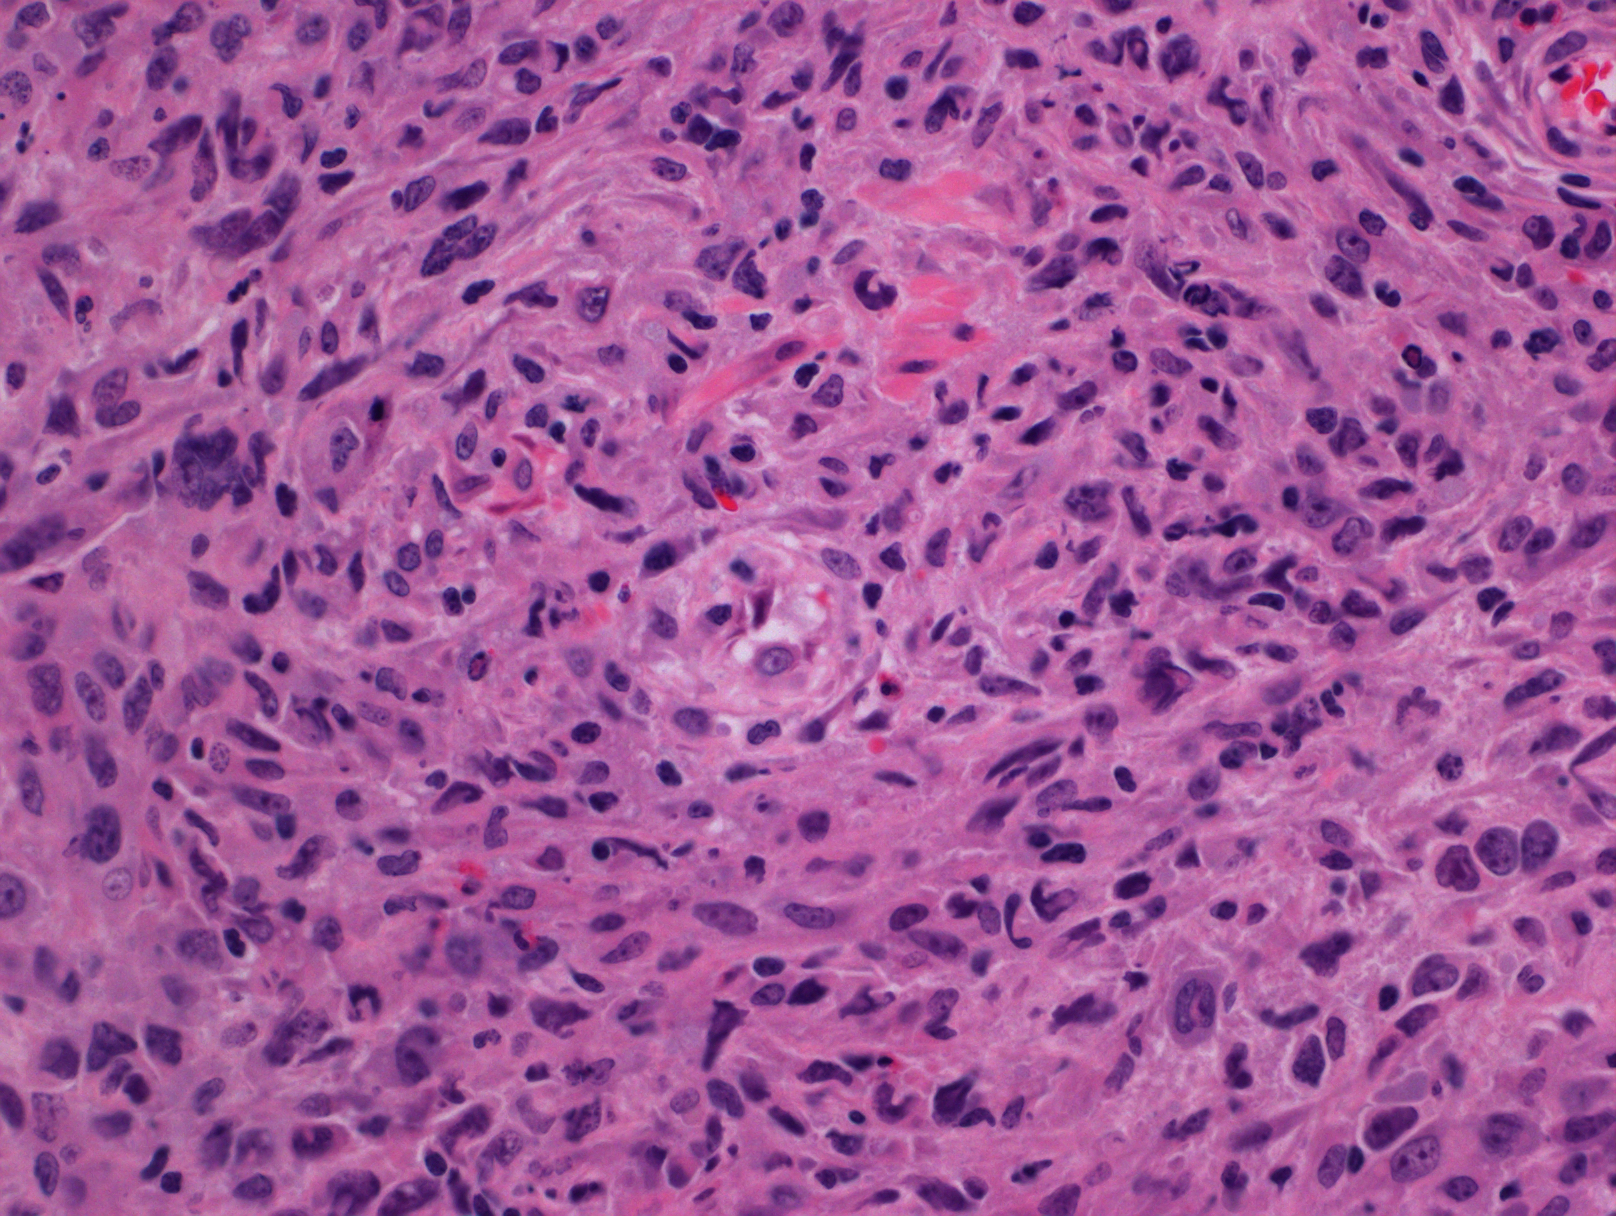

弥漫生长模式,表性为相对丰富的 HRS 细胞和较少的非肿瘤性淋巴细胞。粒细胞、嗜酸细胞、浆细胞希疏或罕见。

根据肿瘤细胞形态和分布及背景成分,可分为两种生长模式:弥漫纤维化型(含丰富纤维母细胞和纤维间质,但不形成胶原纤维束,含大量组织细胞和一些小淋巴细胞毒,但很少噬酸细胞和浆细胞);肿瘤细胞丰富型(大量间变样、多形性 HRS 细胞,有时类似肉瘤)。